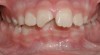

Although most orthodontic treatment begins between the ages of 9 and 14,1 a number of problems are most effectively treated at an earlier age, as delineated in Table 1. Although it is outside the scope of this article to discuss in detail each item listed, the case of excessive protrusion of upper incisors provides insight into the importance of referring patients to the orthodontist in a timely fashion. According to Proffit, there is an approximately 33% chance that a patient with excessive overjet will experience trauma to the upper incisors (Figure 2), thus a prompt referral is essential to greatly decrease the risk of potential trauma.2

Figure 2 A 10-year-old patient with excessive overjet who fractured a protruding maxillary incisor.

Figure 2